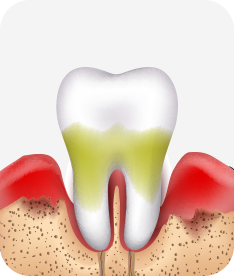

치주치료

청담네오플란트는 치주치료를 통하여 치아를 살릴 수 있는 기회를 놓치지 않습니다.

치주염(잇몸병)은 치아에 붙어있는 치석 및 세균 등에 의한 염증반응으로 잇몸뼈가 상실되는 질환을 말합니다.

초기에는 잇몸이 붓거나 잇몸에서 피가 나는 증상이 나타나며 계속 방치하면 치아를 발치해야 할 수도 있습니다.

치주치료는 이러한 치석 및 세균 등을 제거하여 잇몸뼈를 안정된 상태로 유지하는 시술을 말하며, 청담네오플란트에서는 치의학박사 / 전문의가 직접 시술하고 있습니다.

치주염 단계별 증상

치은염 (초기~중기)

치아 주위의 잇몸이 붉게 부어 있으며, 칫솔질 등을 할 때 피가 남.

스케일링 주기의 조절이 필요할 수 있으며, 올바른 칫솔질을 시행하여야 함.

치주염 (중기~말기)

주기적으로 잇몸이 붓고 피가 나며, 욱씬하거나 우리한 통증이 나타남.

치주치료 및 정도에 따라 치주수술(잇몸수술)이 필요함. 향후 관리 정도에 따라 3~6개월 간격으로 내원하여 유지치료를 시행하여야 함.

치주염 (말기)

잇몸이 항상 부어 있으며, 이가

흔들리는 정도가 점점 심해짐.

치주치료가 필요하며, 정도에 따라 치아를 발치하여야 할 수 있음.